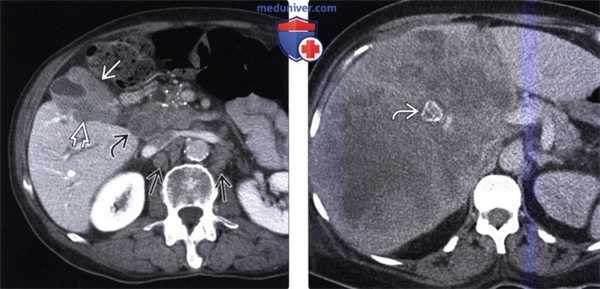

(Слева) На аксиальной КТ с контрастным усилением определяется рак желчного пузыря с инвазией в печень и нисходящую часть двенадцатиперстной кишки. Такие опухоли, если признаются резектабельными, однозначно требуют выполнения расширенной холецистэктомии и радикальной резекции.

(Справа) На аксиальной КТ с контрастным усилением визуализируется объемное образование в ямке желчного пузыря, прорастающее в печень. Во многих случаях, в том числе и в этом, место происхождения опухоли сложно определить.

(Слева) На аксиальной КТ с контрастным усилением определяется выраженное неравномерное утолщение стенки желчного пузыря, непосредственная инвазия печени, а также перипанкреатическая/портокавальная и забрюшинная лимфаденопатия. Увеличение лимфатических узлов этих групп является типичным проявлением рака желчного пузыря.

(Справа) На аксиальной КТ с контрастным усилением визуализируется большое гиподенсное образование в печени. Это образование может быть опухолью печени, однако желчный камень в его центре и невозможность визуализации желчного пузыря позволяют предположить, что образование представляет собой рак желчного пузыря с инвазией печени.